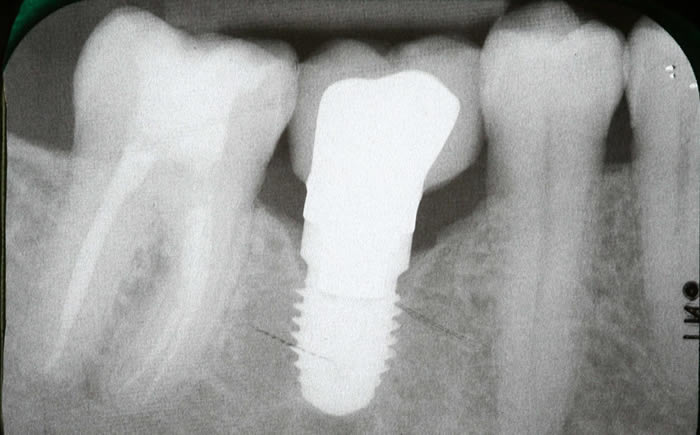

More back teeth replaced by dental implants

Case Three (2 images)

Case Four (4 images)

Case Five (4 images)

Case Six (8 images)

Case Seven (4 images)